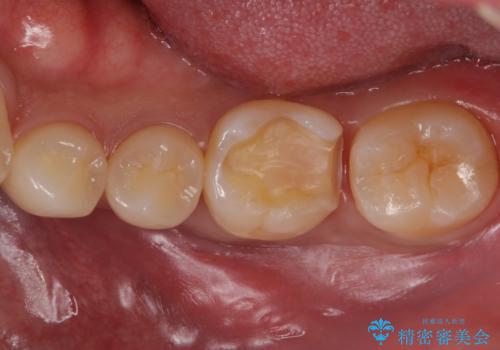

奥歯が欠けた セラミックインレーでの治療

- 奥歯が欠けたとのことで来院されました。

白い詰め物をご希望されたため、セラミックインレーでの治療を行います。

治療前後で比べると、詰め物と歯の間のすき間もなくなりセラミックインレーの適合の良さが伺えます。